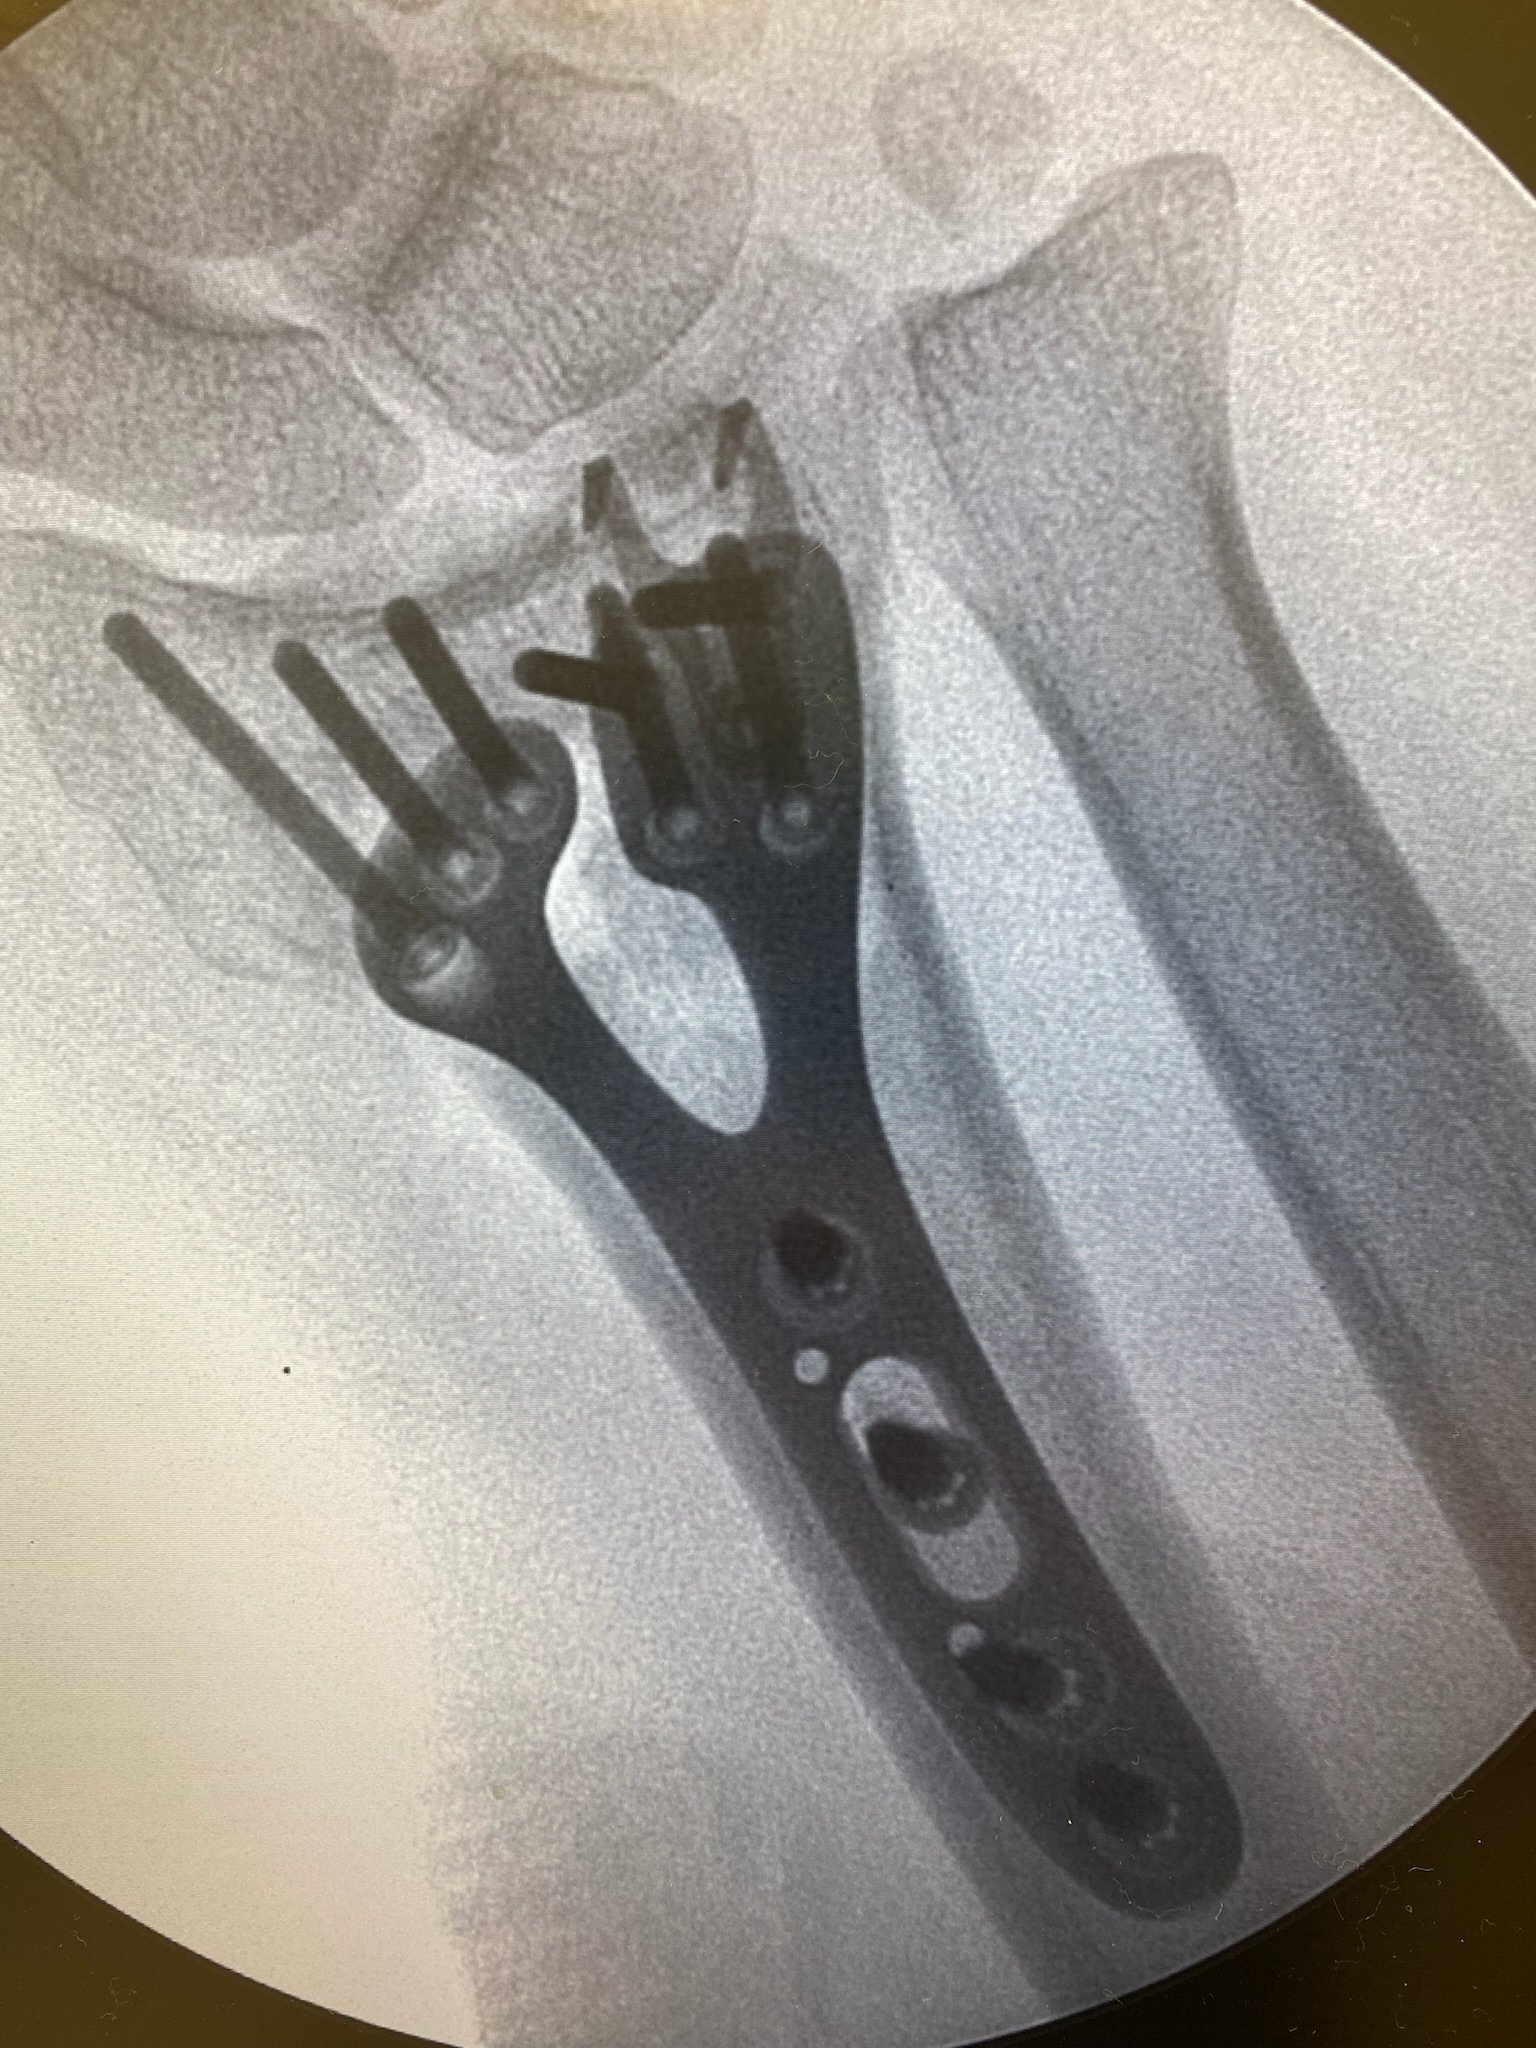

Skeletal Dynamics is proud to be the only medical device company solely focused on the upper extremity.